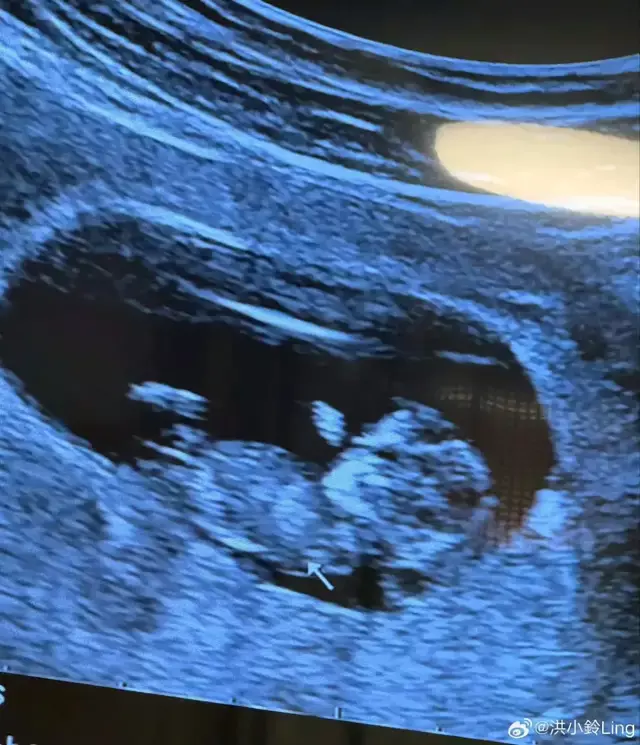

不过没想到的是这么快就有孩子了,果然缘分到了结婚生子其实就是一瞬间的事。

况且他们还有了爱的结晶太平洋在线真人百家乐,从二人世界到三口之家,是他们共同期许的,这样的爱情很难让人不羡慕,祝福。